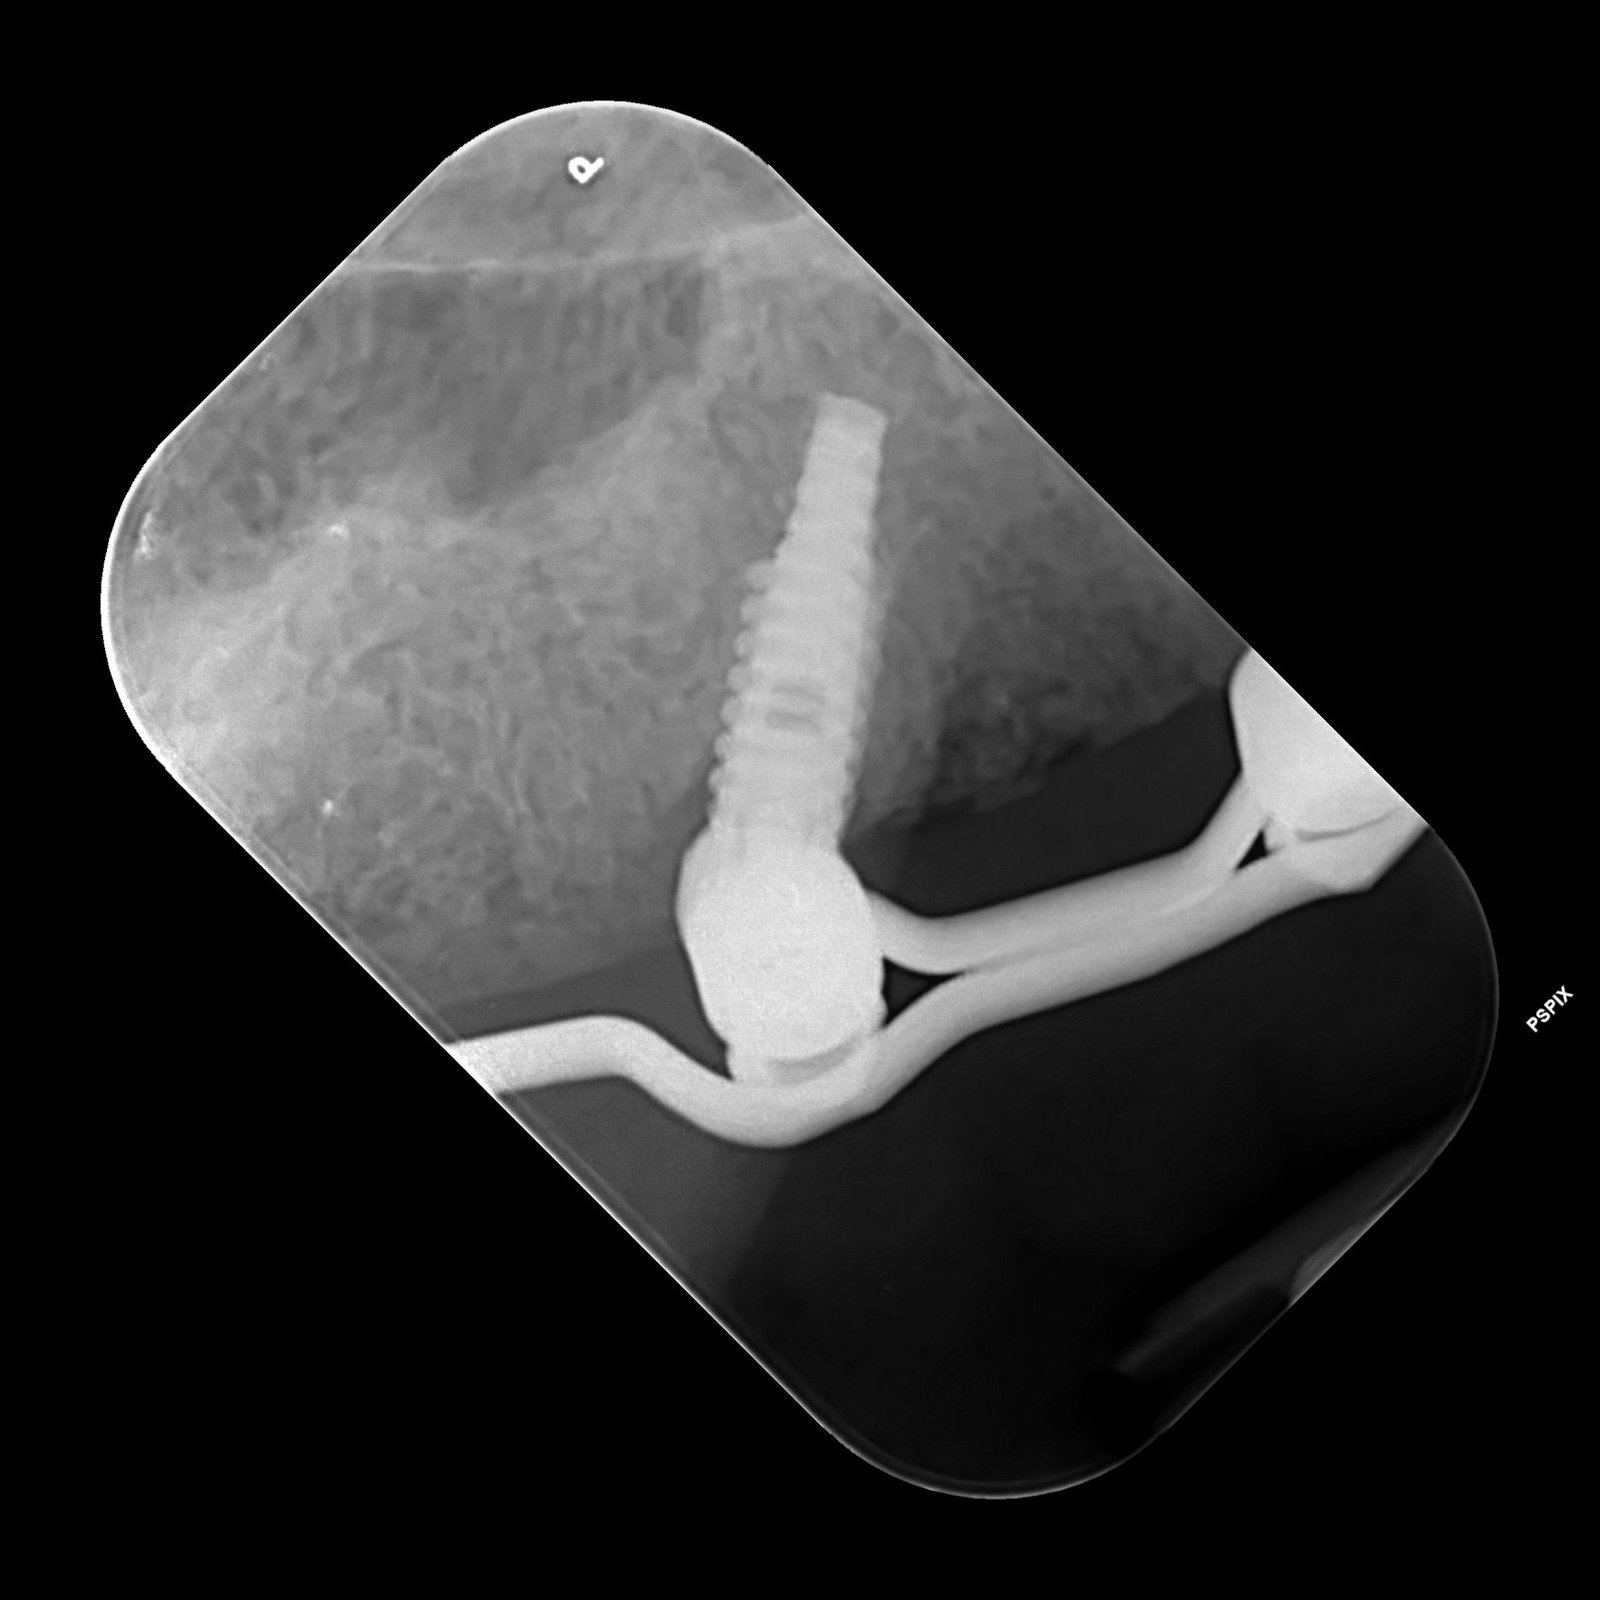

Buenos días, tengo este caso de implante fracasado de un puente de 4 unidades de 24 a 27. La paciente se quejará de que algo se movía, quité el puente [...]